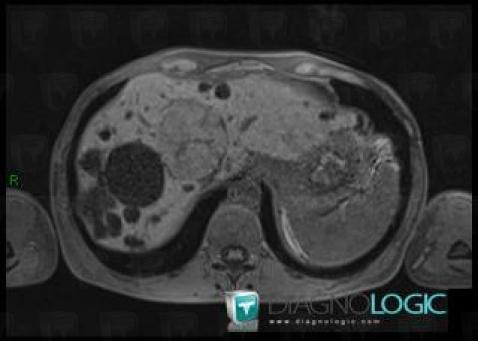

Hyperplasie nodulaire focale, Foie, IRM

Voici les informations spécifiques à l'image clé ci dessus:

- Diagnostic Hyperplasie nodulaire focale, Localisation(s) Foie, comportant les gammes Lésion hépatique en hypersignal T1

Polykystose rénale, Rein, IRM

- Diagnostic Polykystose rénale, Localisation(s) Rein, comportant les gammes Masse rénale en hypersignal T2, Masse rénale kystique, Maladie kystique rénale

- Diagnostic Polykystose rénale (lié à Kyste ), Localisation(s) Rein, comportant les gammes Masse rénale exophytique